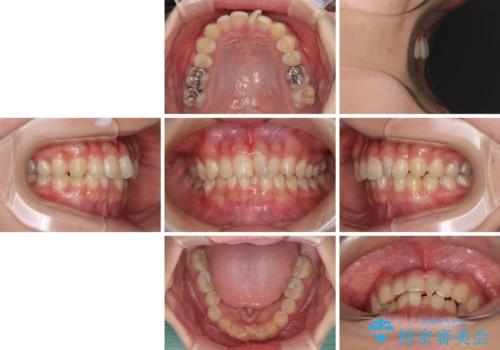

深い咬み合わせとデコボコの歯列をワイヤー矯正で改善

- 前歯のデコボコと深い咬み合わせを改善したいとのことで来院された患者様です。

奥歯の咬み合わせは上顎に対して下顎が後方位にあり、上顎前歯で下顎前歯が隠れるような典型的な過蓋咬合です。

補助装置を用いて上顎大臼歯を後方に移動させながら、ワイヤー装置で歯列を整えて深い咬み合わせを挙上することとしました。

下顎の装置が頻繁に脱落し、治療は難航しましたが、当初予定の2年間で無事に治療を終えることができました。